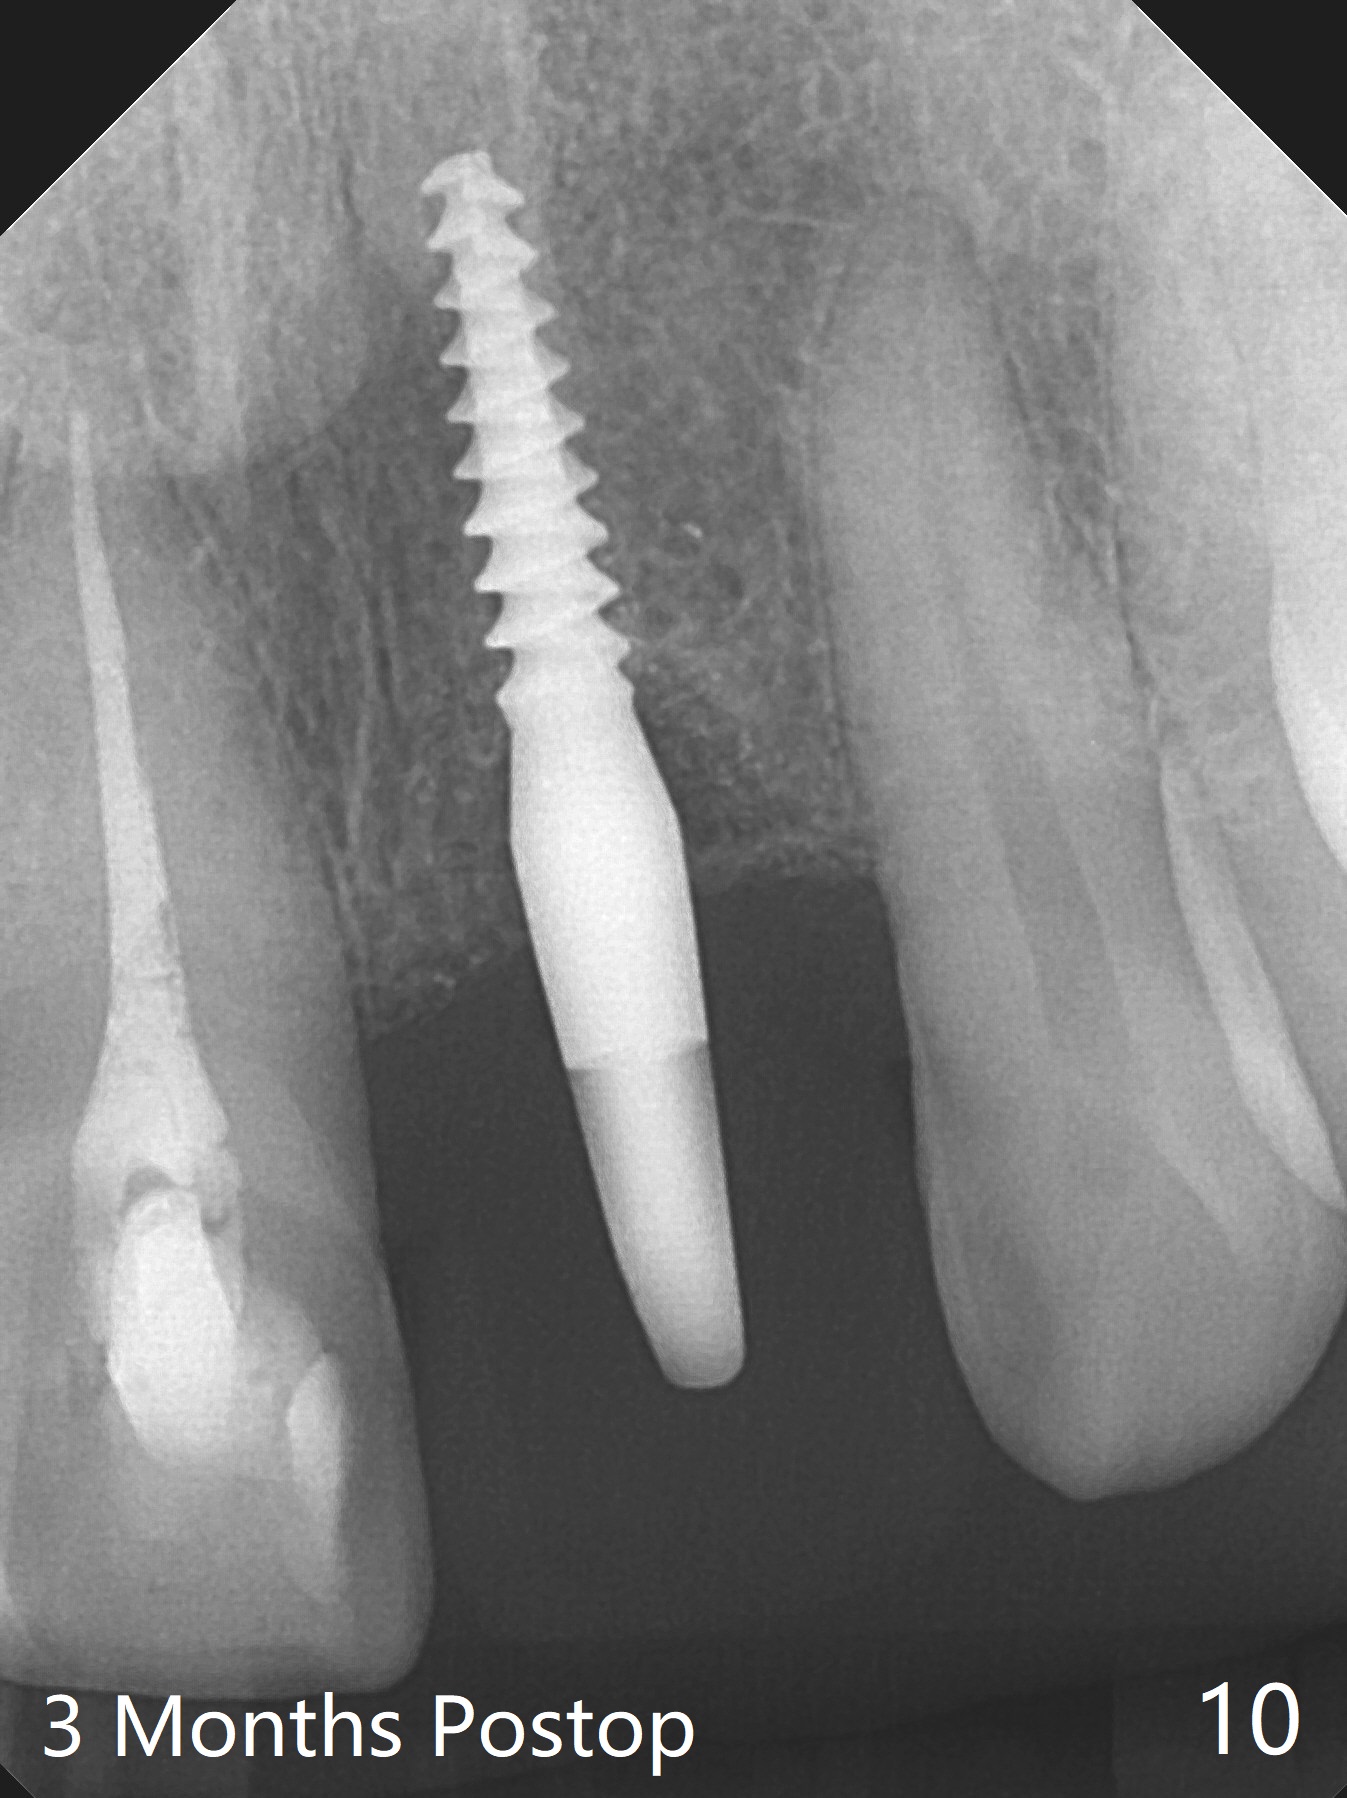

Except the depth, a 2.5x10 mm mini implant is placed with precision (in trajectory) at #9 (Fig.1-5). Confidence using surgical guide for the narrow ridge is enhanced due to placement of two digits against the buccal and palatal plates for tactile sensation. The depth issue is related to overprep with 2.2 mm drills. The torque is <15 Ncm. The immediate provisional is bonded to the neighboring teeth for retention. It appears that smaller drills should be made for guided surgery (such as 1.5 and 2.0 mm). The immediate provisional looks acceptable buccal and occlusal 3 weeks postop (Fig.6,7), although the palatal gingiva is erythematous (Fig.8, which is common after use of drill for access (tissue laceration), OHI offered). Three months postop (Fig.9), the palatal gingiva looks healthy (data not shown), while there is no bone loss around the implant (Fig.10). It remains the same 5 months postop (immediately post cementation, Fig.11) and 3,11 months post cementation (Fig.12,13). The labial gingiva is healthy (Fig.14), while the palatal one is less erythematous and edematous (Fig.15) than earlier (Fig.8).